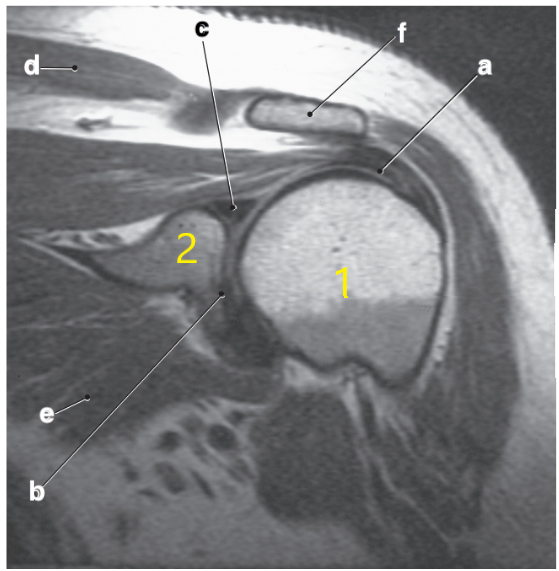

Supraspinatus tendon

Supraspinatus muscle

Acromion

Scapular spine

The oblique coronal views for an MRI of the shoulder need to be oriented ---

Parallel to the supraspinatus tendon